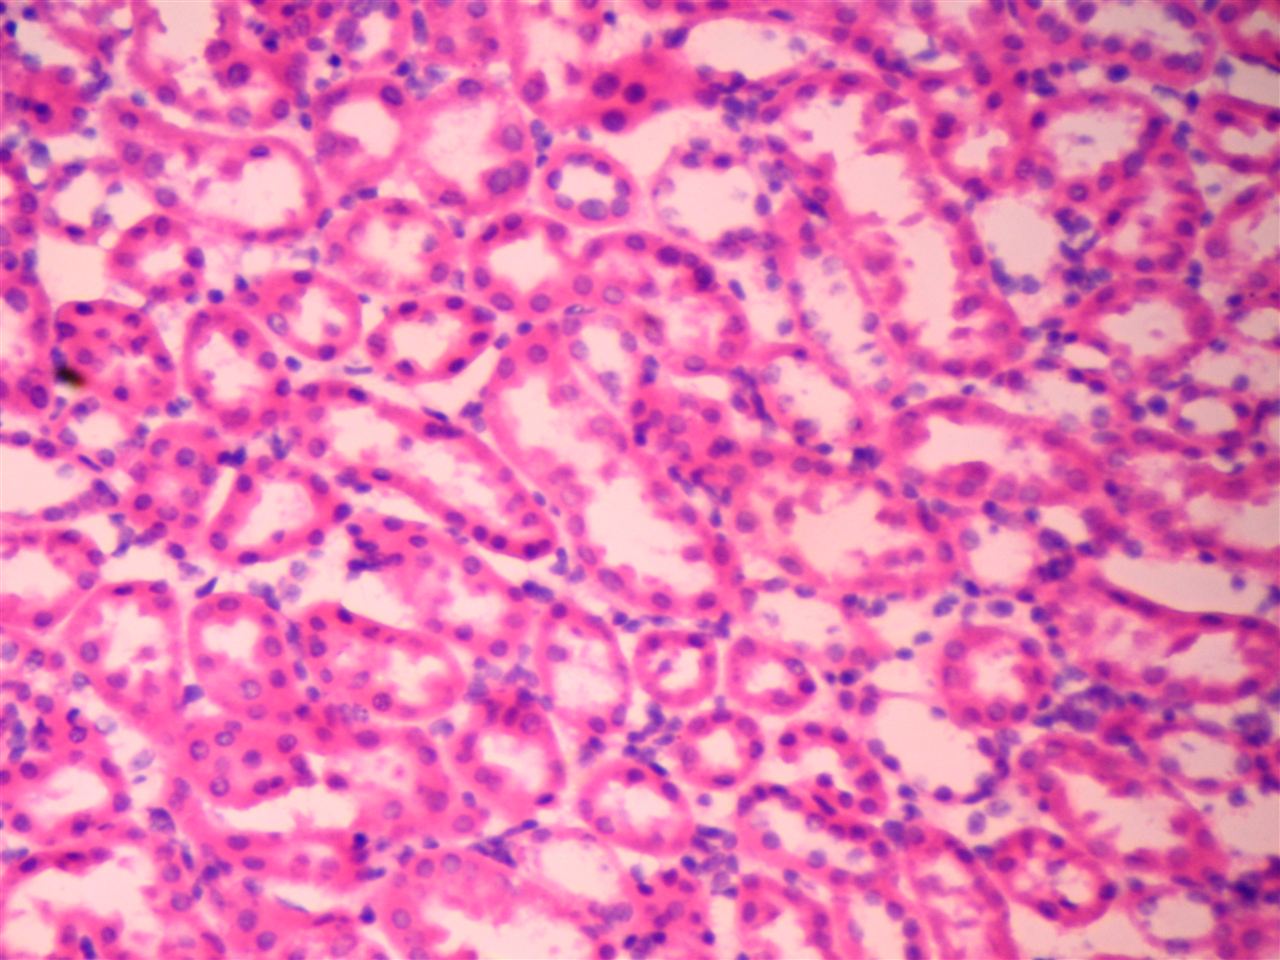

染色结果展示:

瑞氏染色剂G1040瑞氏染色剂G1040瑞氏染色剂G1040瑞氏染色剂G1040瑞氏染色剂G1040瑞氏染色剂G1040瑞氏染色剂G1040